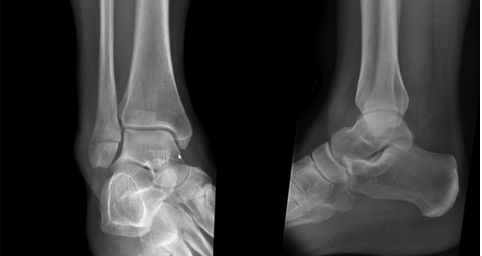

Q

Weber’s B fracture

13

How are Weber’s B fractures managed?

Weber B fractures can be unstable, with further fractures to the fibular, so management depends on stability